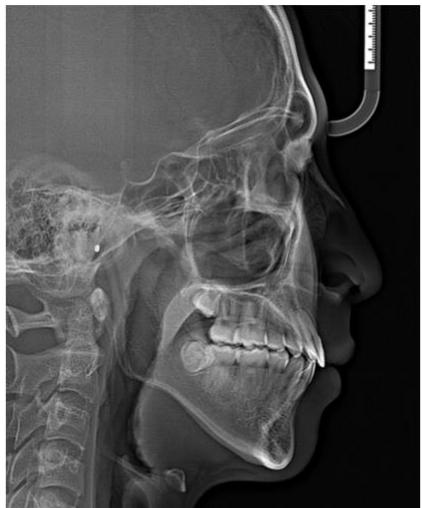

Figure 4: Pre-Treatment Lateral Cephalometric Radiograph

Cephalometric analysis according to the Ricketts system revealed a mild skeletal Class II relationship, with a facial convexity of $3.4 \mathrm{~mm}$ [15]. The mandible was mildly retrusive relative to the cranial base, as indicated by a facial depth of $85.8^{\circ}$, while the maxilla demonstrated a relatively neutral position with a maxillary depth of $88.9^{\circ}$ [15,16].

Vertical analysis demonstrated a pronounced vertical growth pattern, with an increased FMA of $36.7^{\circ}$, an increased lower facial height (LFH) of $48^{\circ}$ (compared with the normal range of $45 - 46^{\circ}$ ), and a reduced facial taper of $57.5^{\circ}$ relative to the average value of approximately $68^{\circ}$ [3,15]. These findings reflect a tendency toward clockwise mandibular rotation and vertical facial imbalance.

Dentally, both maxillary and mandibular incisors exhibited markedly increased proclination and protrusion compared with physiological norms (maxillary incisors: protrusion 13.3 mm, inclination $41.6^{\circ}$; mandibular incisors: protrusion 10.7 mm, inclination $36.1^{\circ}$ [6,15]. Overall, this case represents severe bimaxillary incisor protrusion on a background of mild skeletal Class II malocclusion with a high-angle growth pattern, accompanied by an unfavorable biological risk factor characterized by the close proximity of the mandibular incisor roots to the labial cortical plate [10-12].